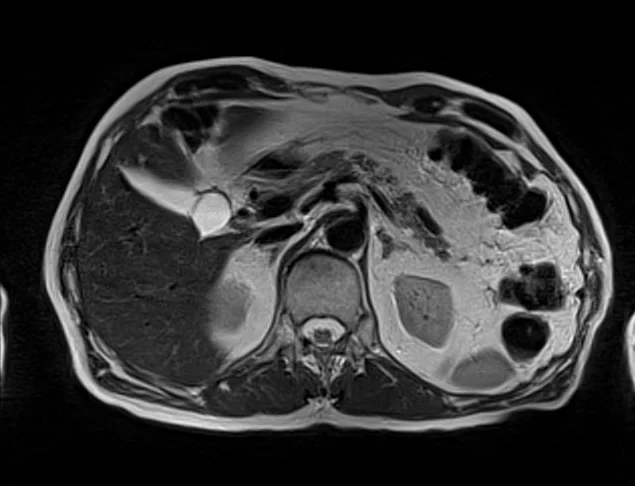

mrimaster

t2 3 - MRI